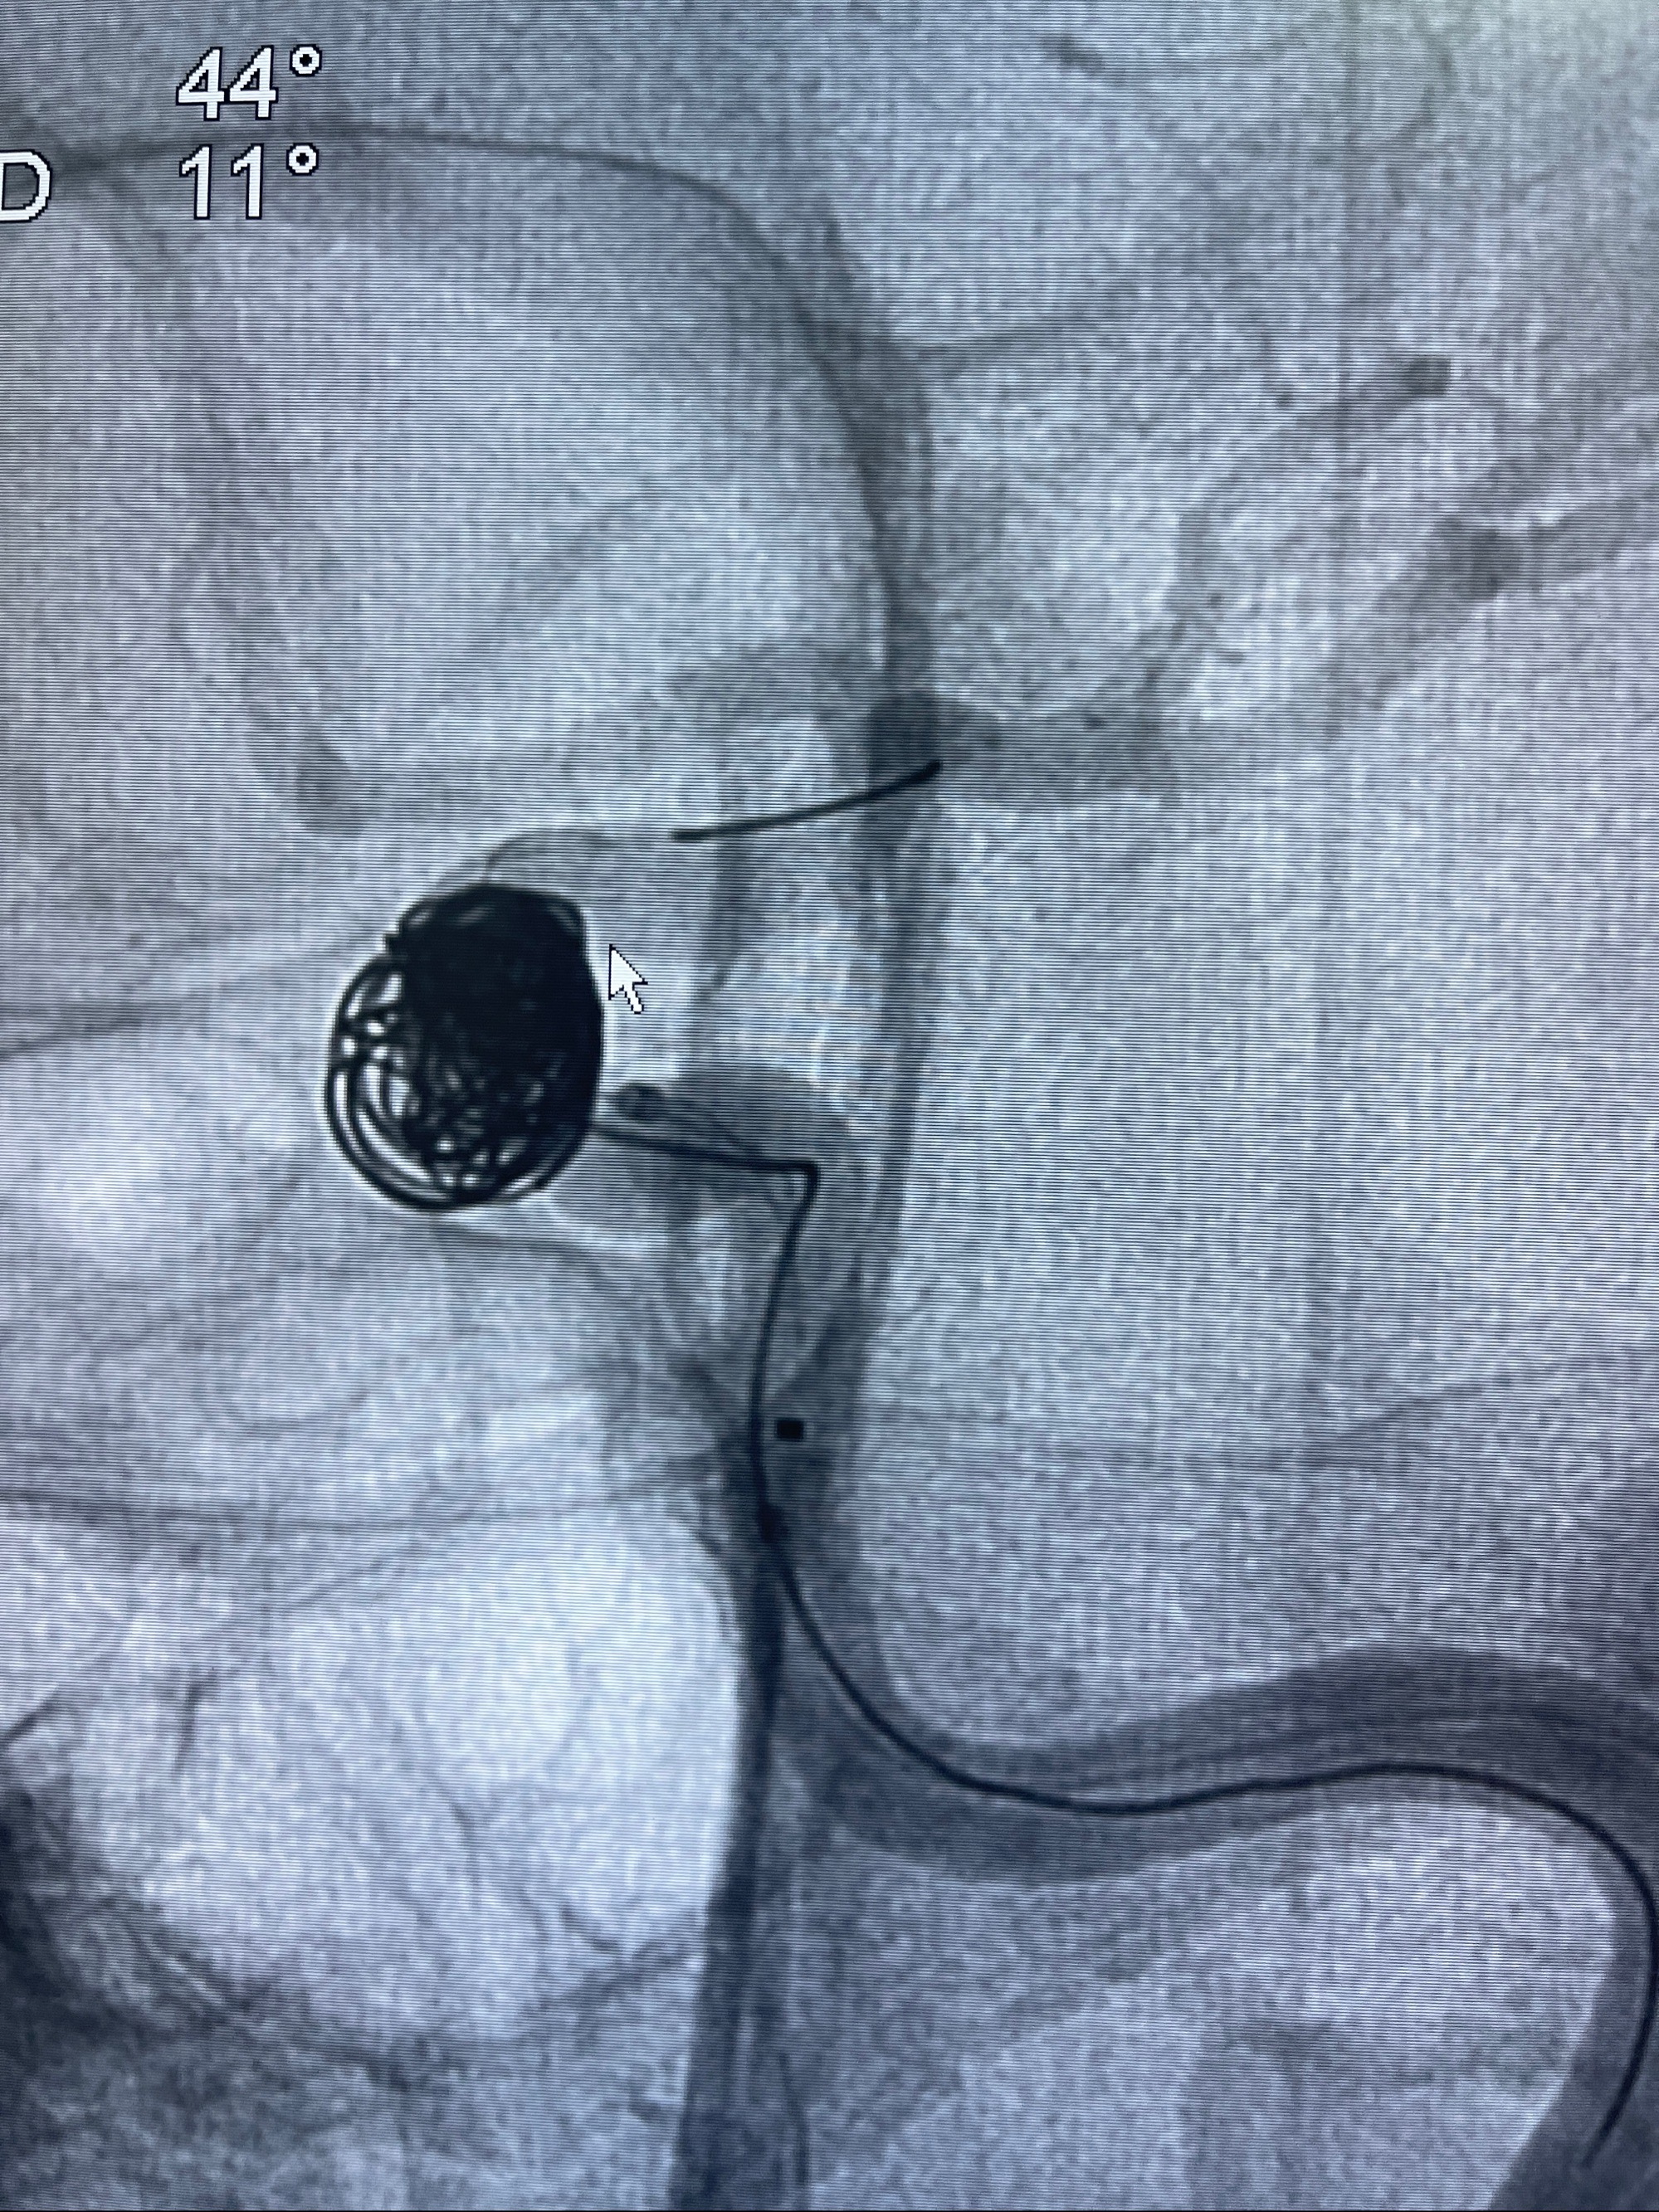

2023-08-30DSA:左侧颈内动脉眼动脉动脉瘤,约3*9.2*7.3mm大小

密网支架辅助栓塞

- Tubridge 4.0-20mm密网支架

- 加奇微弹簧圈:7*30/6*20/5*20/2*8

术后3D显示支架贴壁佳